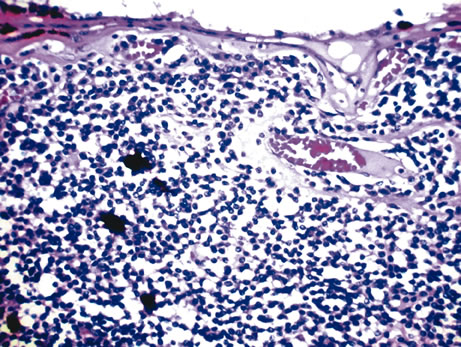

Three histologic patterns of granulomatous inflammation may be seen: diffuse, discrete, and zonal. In diffuse granulomatous inflammation, the epithelioid histiocytes are scattered throughout the involved uveal tissue (Fig. 19). There may be an accompanying background of lymphocytes and plasma cells. Discrete granulomatous inflammation reveals well-circumscribed areas of epithelioid histiocytes (Fig. 20). Zonal granulomatous inflammation consists of a central zone of necrosis and/or polymorphonuclear leukocytes surrounded by epithelioid histiocytes, which is in turn surrounded by a zone of non-granulomatous inflammation consisting of granulation tissue, lymphocytes and plasma cells (Fig. 21).

Fig. 19. Sympathetic ophthalmia. Diffuse granulomatous inflammation involving the choroid. (Hemotoxylin-eosin ×65.)

Fig. 20. Sarcoidosis. Discrete granulomatous inflammation is seen in sarcoidosis. (Hemotoxylin-eosin ×100.)

Fig. 21. Tuberculous choroiditis. A zonal granulomatous inflammation is present. Central area shows necrosis. (Hemotoxylin-eosin ×65.)